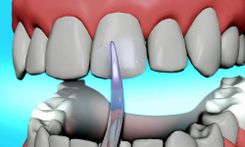

Direkt ve İndirekt Kompozit Lamina

Lamina Uygulamaları

Laminate Veneer

Porselen Laminate Veneer

Yaprak Kompozit Lamina